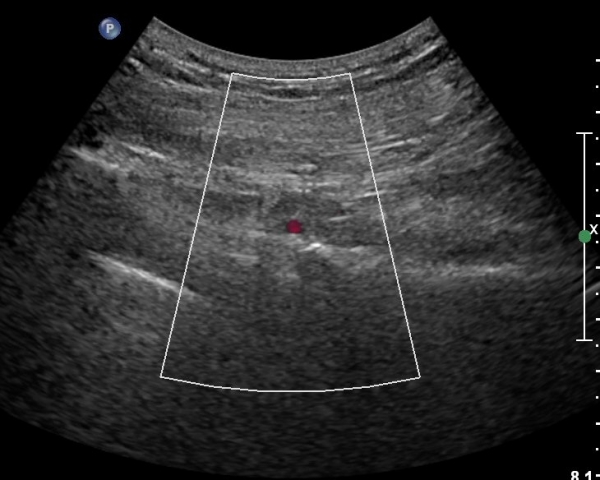

ŽÃËÀÚ¸¦ ´ëÀüÀÚ°¡ º¸À̵µ·Ï ¿ÜÃøÀ¸·Î À̵¿Çϸé Á°ñÇ¥Ãþ¿¡ ´ëÀüÀÚ·Î ÁÖÇàÇÏ´Â ÀÛÀº ³×°³ÀÇ ±ÙÀ°ÃþÀÌ °üÂûµÇ´Âµ¥ ¸Ó¸®ÂÊ¿¡¼­ ¾Æ·¡·Î SG, OI, IG, QF¸¦ °üÂûÇÒ ¼ö ÀÖ°í, ÀÌ ±ÙÀ°µé Ç¥Ãþ¿¡¼­ °í¿¡ÄÚ·Î °üÂûµÇ´Â Ÿ¿øÇü ±¸Á¶¹°ÀÌ Á°ñ½Å°æÀÌ´Ù(»çÁø 4, 5, 6, 7).